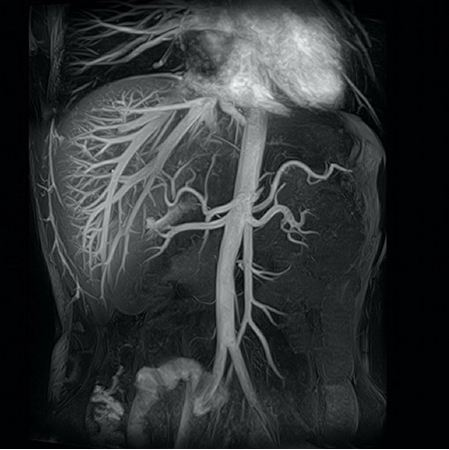

2.- También podemos incluir gestión post proceso de la imagen a través de tecnologías que mantengan la Precisión Diagnóstica en los tejidos y hallazgos. Entiendo que llegará una tecnología para el CT parecida a la que usa Toshiba con su software (Time-SLIP: Spatial Labeling Inversion Pulse) para Resonancia que evita el contraste de resonancia y que ofrece esta imagen:

Con estas tecnologías: ¿podemos reducir las dosis de barrido en el URO TC?